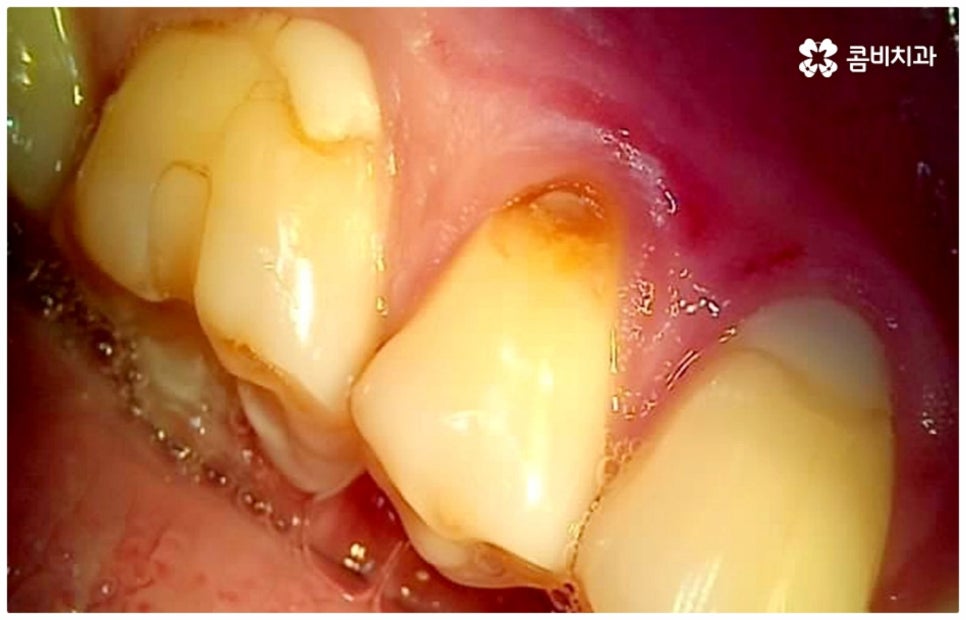

평상시에 꼬박꼬박 검진이나 스케일링 치료를 받으시는 분들이 점차 많아지고 있는 반면 시간이 없어서 또는 막연한 두려움으로 인해서 더 이상 통증을 참을 수 없을 지경에 이르러서야 치과에 가시는 분들도 있을 거예요. 그런 경우 대부분 내원을 하신 시점에 이미 치아 내부 손상이 상당하고 살릴 수 있는 자연 치아가 굉장히 적을 수 있어요. 그러므로 이 중 몇몇 케이스는 굉장히 복잡한 고난도의 신경치료 대상이 될 수 밖에 없으며 혹시라도 미세한 부근관의 감염을 놓치게 되면 재신경치료를 해야 할 수도 있습니다. 이럴 때는 신경치료를 받은 후에 얼마 지나지 않아 해당 치아를 쓸 수 없게 되는 결과가 나올 수도 있는데요. 그러면 어금니충치치료 를 하여 괜히 힘만 두 번 들이고 고생을 하는 것 보다는 바로 임플란트 단계로 가는 것이 낫지 않느냐고 문의를 주시는 분들도 있어요.

그러나 요즘 임플란트 관련 기술이 많이 발달하여 자연 치아 상실에 대처하는 가장 대표적인 인공 치아 시술로 손꼽히고 있다고 해도 구조적인 차이점으로 인해 타고난 치아와 똑같을 수는 없다는 점, 자칫 관리에 소홀하면 잇몸 질환에 취약하여 주변 치아까지 좋지 않은 영향을 받을 수도 있다는 점 등을 고려해 봤을 때 구강 건강을 위해서는 될 수 있는대로 자연 치아의 수명을 늘리는 것이 보다 의미가 있습니다.

사실상 신경치료나 재신경치료가 어금니충치치료 중 거의 마지막 단계의 보존 치료에 속하는 것임을 감안해 봤을 때 해당 치료를 받은 자연 치아의 수명이 얼마나 될까 궁금해 하시는 분들도 있는데요. 환자분들의 상황에 따라 다르지만 신경 치료를 한 치아의 평균 수명은 약 11년 정도 (후속 처치인 크라운 치료를 함께 받았을 경우 약 20년까지 수명이 늘어남) 라는 연구 결과가 있는 만큼 치료 시기를 놓치지 않도록 주의를 기울이고 관리하면서 필요하다면 바로 뛰어난 노하우를 가지고 있는 숙련된 의료진에게 꼼꼼하게 신경 치료를 받을 수 있도록 하는 것이 중요한 포인트라고 할 수 있어요.